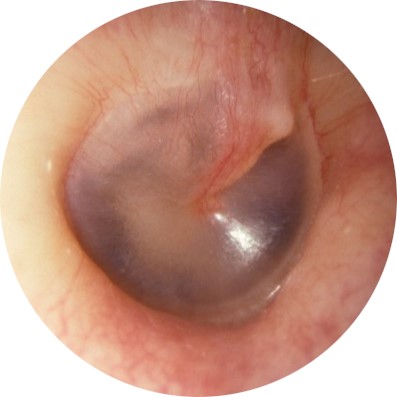

| LEVEL | DESCRIPTION | PICTURE |

| TEED 0 | Normal tympanic membrane. No evidence of injury despite the presence of symptoms. |

|

| TEED 1 | Diffuse redness and retraction of tympanic membrane. Erythema over part of the tympanic membrane due to inflammation, particularly around the manubrium. |

| TEED 2 | Diffuse redness and retraction of tympanic membrane, plus slight hemorrhage within the tympanic membrane. |

| TEED 3 | Diffuse redness and retraction of tympanic membrane, plus gross hemorrhage within the tympanic membrane. |

| TEED 4 | Dark and slightly bulging tympanic membrane due to free blood in the middle ear (a fluid level may also be present). |